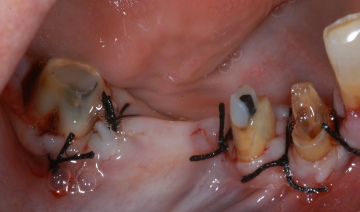

ΧΕΙΡΟΥΡΓΙΚΗ ΕΠΙΜΗΚΥΝΣΗ ΜΥΛΗΣ ΔΟΝΤΙΩΝ ΠΡΙΝ ΤΗΝ ΠΡΟΣΘΕΤΙΚΗ ΑΠΟΚΑΤΑΣΤΑΣΗ

ΠΡΙΝ